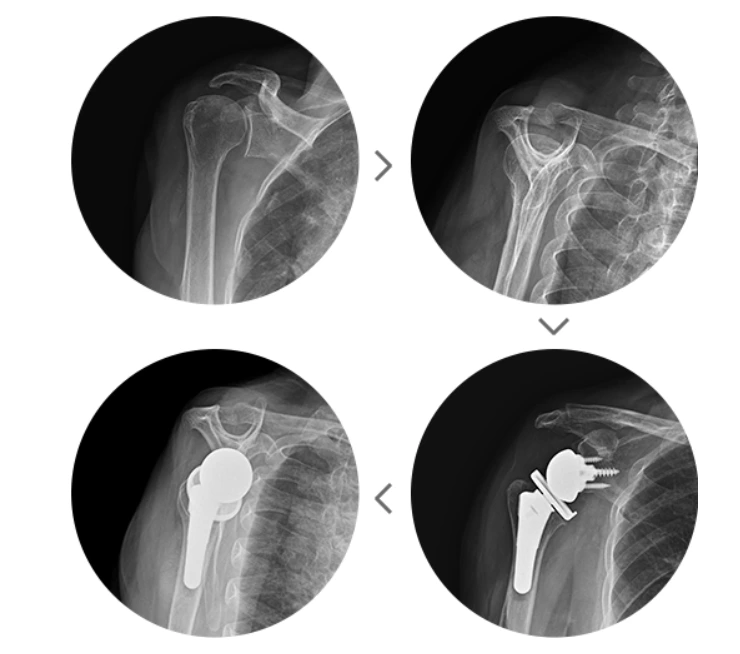

수술을 할 때는 관절내시경을 통한 선별적 수술을 시행하는데요. 대표적으로 회전근개 힘줄이 붙어 있는 자리의 내측에 無나사봉합사를 삽입하고 특수 바늘을 이용해 잇는 브릿지 이중 봉합술, 피부와 동일한 동종진피로 소실된 힘줄을 대체해 봉합하는 타가 힘줄 이식술, 광범위한 회전근개파열로 인해 가성마비까지 발생한 경우에 시행하는 역행성 인공관절 치환술이 있습니다.